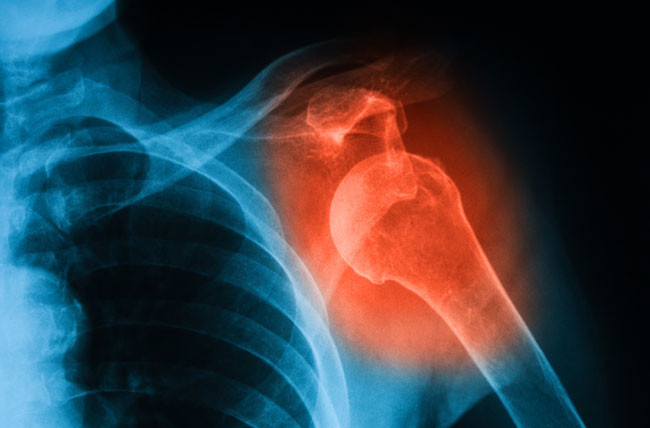

• X-ray

Tulang rawan tidak terlihat pada X-ray, namun penurunan atau hilangnya tulang rawan akan tampak sebagai penyempitan celah di antara dua tulang pada suatu sendi.